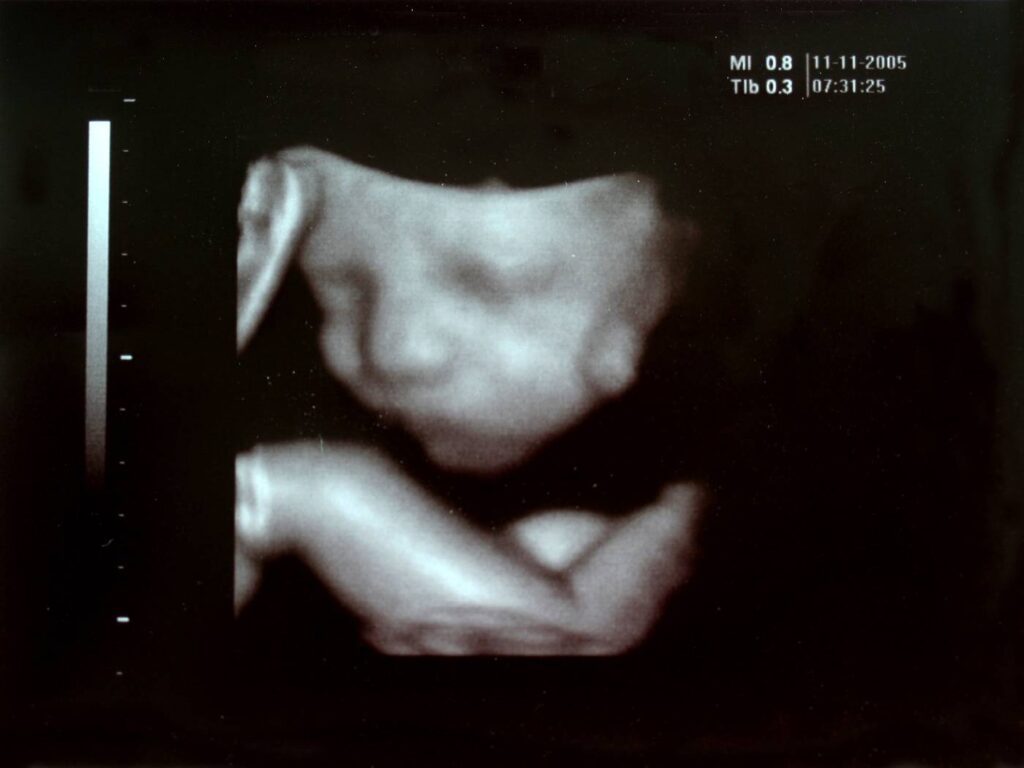

Preborn babies move a lot, and pregnant women notice the movements. An ultrasound scan is often done at 20 or 21 weeks to assess anatomy, and the scan can reveal the sex of the preborn baby for couples who want to know.